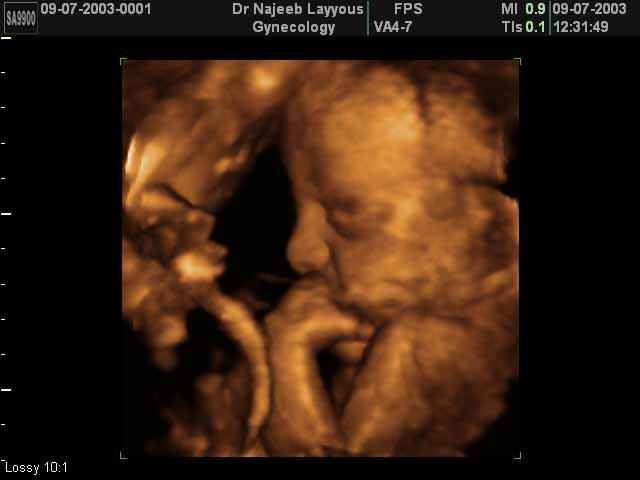

- 3D Fetal Profile Ultrasound Scan Photos

3D Fetal Profile Ultrasound Scan Photos | Dr N Layyous